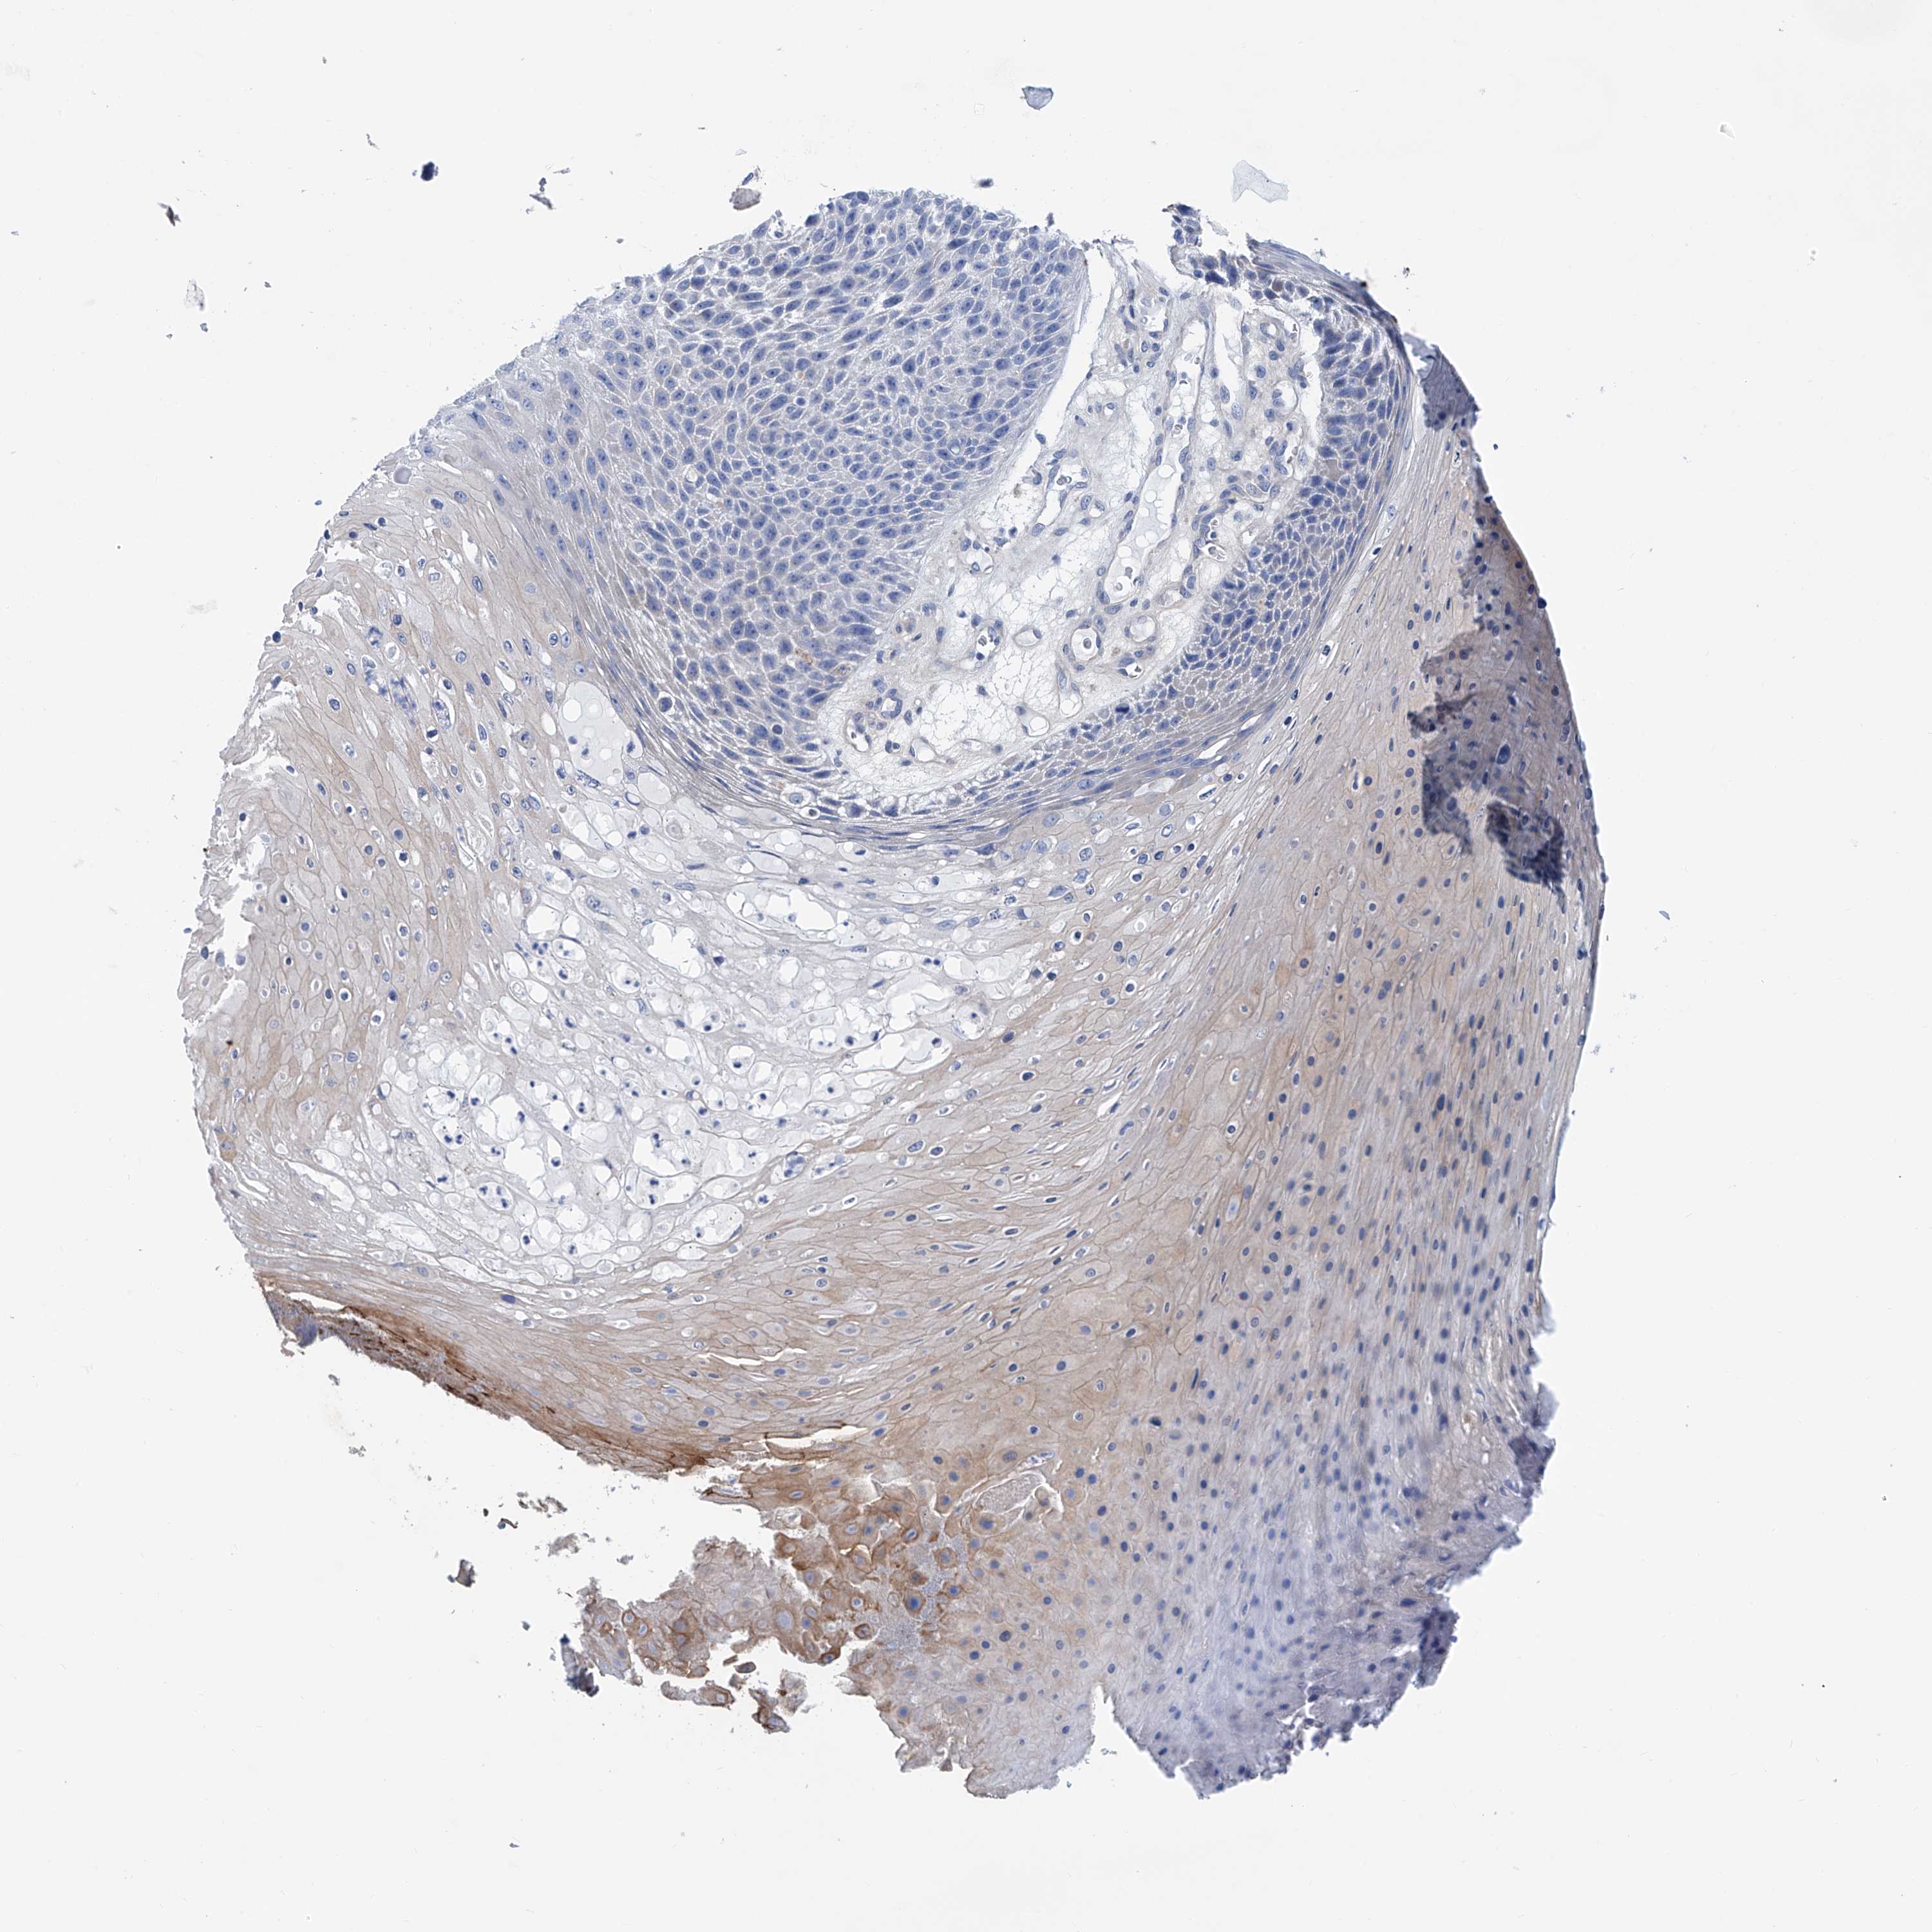

SKIN CANCER - Protein expressioni

A mouse-over function shows sample information and annotation data. Click on an image to view it in a full screen mode. Samples can be filtered based on level of antibody staining by selecting one or several of the following categories: high, medium, low and not detected. The assay and annotation is described here.

Antibody stainingi

Antibody staining in the annotated cell types in the current human tissue is reported as not detected, low, medium, or high, based on conventional immunohistochemistry profiling in selected tissues. This score is based on the combination of the staining intensity and fraction of stained cells.

Each image is clickable and will lead to virtual microscopy that enables deeper exploration of all samples and also displays staining intensity scores, fraction scores and subcellular localization as well as patient and tissue information for each sample.

Antibody HPA026726

Antibody HPA026764

Antibody CAB010907

Staining

High

Medium

Low

Not detected

Squamous cell carcinoma, metastatic, NOS

Squamous cell carcinoma, NOS